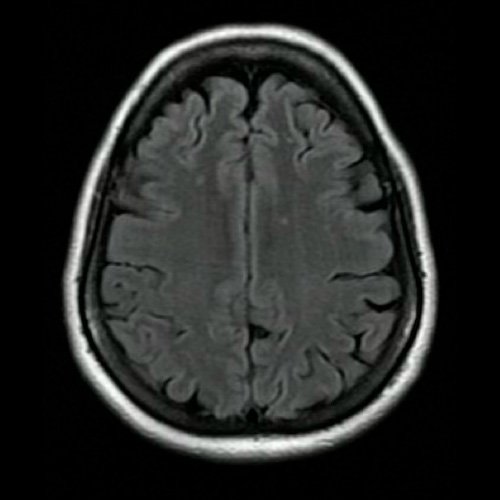

Curso internación en sala general y fue evaluada en conjunto con servicio de Neurología por síndrome atáxico en estudio. A su ingreso, se realizó Angio resonancia de cráneo que no evidenció alteraciones, se realizó una punción lumbar sin hallazgos de jerarquía, con posterior resultado negativo para virus de varicela zoster y herpes simple.

Anexo 2. Angio RMI de cráneo: Corte transversal. Secuencia t2 flair